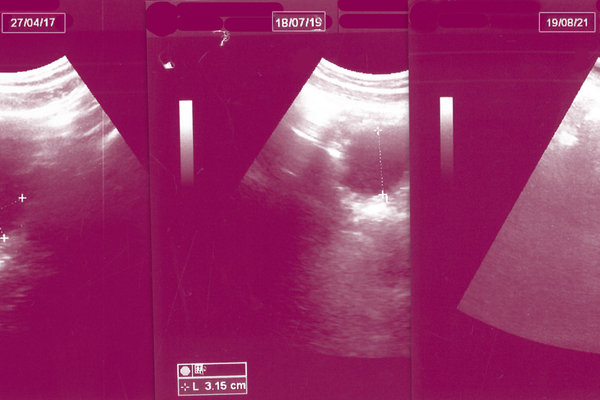

تقول مي الرفاعي، طبيبةٌ نسائيةٌ وناشطةٌ في مجال الصحة الإنجابية، إنّ الطبيب يكون ملزمًا بالإجهاض في حالاتٍ محدّدةٍ تتضمّن عدم ظهور نبض الجنين أو توقّفه، وحالات الحمل العنقودي، وحالات الحمل بأطفال متلازمة داون (إذا ما رغبت الأم بالإجهاض)، وحالات الافتقار إلى عظام الجمجمة، ووجود تشوّهاتٍ كبرى في الهيكل العظمي أو الإصابة بعيوب القلب الأساسية. كما يُسمح بالإجهاض إذا كان الحمل يعرّض حياة الأم للخطر، مثل إصابتها بجلطاتٍ في المخّ أو الشرايين التاجية أو الشريان الرئوي، أو خضوعها سابقًا لعددٍ كبيرٍ من الولادات القيصرية، أو بسبب ضعف جرح القيصرية الذي قد يسبّب انفجارًا في الرحم ونزيفًا خطيرًا في حال حدوث حمل. وتضيف الرفاعي بأن هناك ظروفٌ اجتماعيةٌ تحتّم على الطبيبة إجراء عمليات الإجهاض، مثل حالات التأخر في القدرة العقلية عند الزوجة وحالات اغتصاب القاصرات، مضيفةً أن الأمر رهنُ ضمير الطبيب وحده، فهو من يستطيع أن يقرّر بين نعمٍ أو لا.